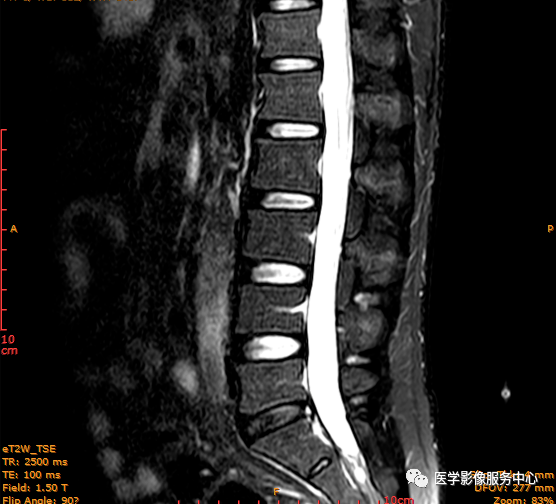

临床诊断 :腰突症?故行腰椎MRI检查,图像如下:

矢状位PD压脂序列

T2矢状位

T1矢状位

这个患者腰椎间盘膨出程度不明显,神经根没有明显的受压,椎管未见明显狭窄,那这个患者腰疼的“罪魁祸首”是腰椎间盘膨出嘛?

大家有没有留意到还有哪个地方不正常呢?

L3-4椎间盘后缘可见点状高信号区(红色箭头所指处)

红色箭头所指的异常信号区是是什么呢?平时工作中大家有没有遇到这种情况,你会不会忽略这个异常信号?有没有想过这个椎间盘后缘高信号区是引起患者腰疼的重要因素呢?下面为大家重点介绍。